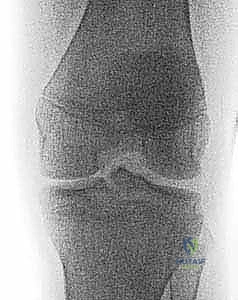

2. التصوير بالأشعة السينية (X-rays)

هي الخطوة الأولى والأساسية. يطلب الدكتور هطيف صوراً بأوضاع متعددة:

* صورة أمامية خلفية (AP): لرؤية الهيكل العام.

* صورة جانبية (Lateral): وهي الأهم لرؤية شوكة الظنبوب وتقييم درجة ارتفاعها وإزاحتها (لتحديد تصنيف مايرز ومكيفير).